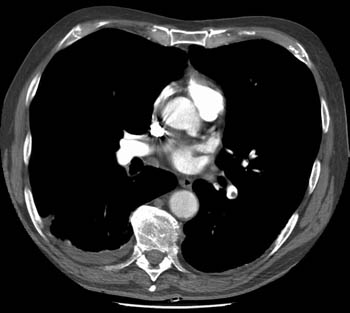

Scott WilliamsAutoimmuneAutoimmune > Sarcoid > Images > Sarcoid3April 2, 2002Central Nervous SystemCNS > CSF imagingApril 2, 2002PETPET Myocardial ImagingApril 2, 2002CardiacCardiac > Adultdz > ProstheticApril 2, 2002Pulmonary ImagingGeneral > BiopsyApril 2, 2002AutoimmuneAutoimmune > Wegener > Images > Case1April 2, 2002Vascular AbnormalitiesVascular > PE > Images > Iliac DVTApril 2, 2002GastrointentinalGastrointestinal > Hepatobiliary > Biliary atresiaApril 2, 2002AutoimmuneAutoimmune > FollbronchApril 2, 2002AutoimmuneAutoimmune > EGApril 2, 2002Previous PagePage 108 of 265Next PageTop StoriesCT5-year CTC screening interval is appropriate for colorectal cancerThe study's findings add to an ongoing conversation about the use of CTC for colorectal cancer screening.MRIASTRO: Daily MRgRT recontouring improves prostate treatment outcomesRadiation Oncology/TherapyASTRO: Radiation therapy comparable to surgery for early-stage lung cancerCTCT use in the ED has more than doubled over a decadeSponsor ContentDigital Innovations Shaping the Future of Radiology